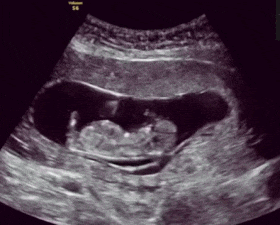

让我们先来看看怀孕4个月意味着什么吧。这时候,胎儿的身长大概10-12厘米,体重大约80-100克,差不多就像一根香蕉那么大。而对于孕妈妈来说,这里可是一个分水岭——之前的3个月那些让人抓狂的孕吐、酸胀感已经逐渐远离,肚子也开始显现出曲线。但,很多夫妻较快地进入“轻松状态”,甚至部分妈妈开始对孕期护理有所松懈。真的可以这么不紧张了吗?专家们对此却泼了一盆冷水:胎儿在这段时间的变化虽然看似平稳,但对于后续发育至关重要,有些隐患一旦忽略,可能为接下来的孕程埋下雷区。

怀孕4个月究竟发生了哪些事?在胎儿这边,这时候的发展可以说进入了“稳定扩建”阶段:胎盘已经完全形成,皮肤虽薄却隐约能见血管,身上的毛发仿佛在搭建一个小型“保暖系统”,而医生在产检中甚至可以捕捉到宝宝那些令人忍俊不禁的小动作,比如“翻滚”“转头”“伸懒腰”。